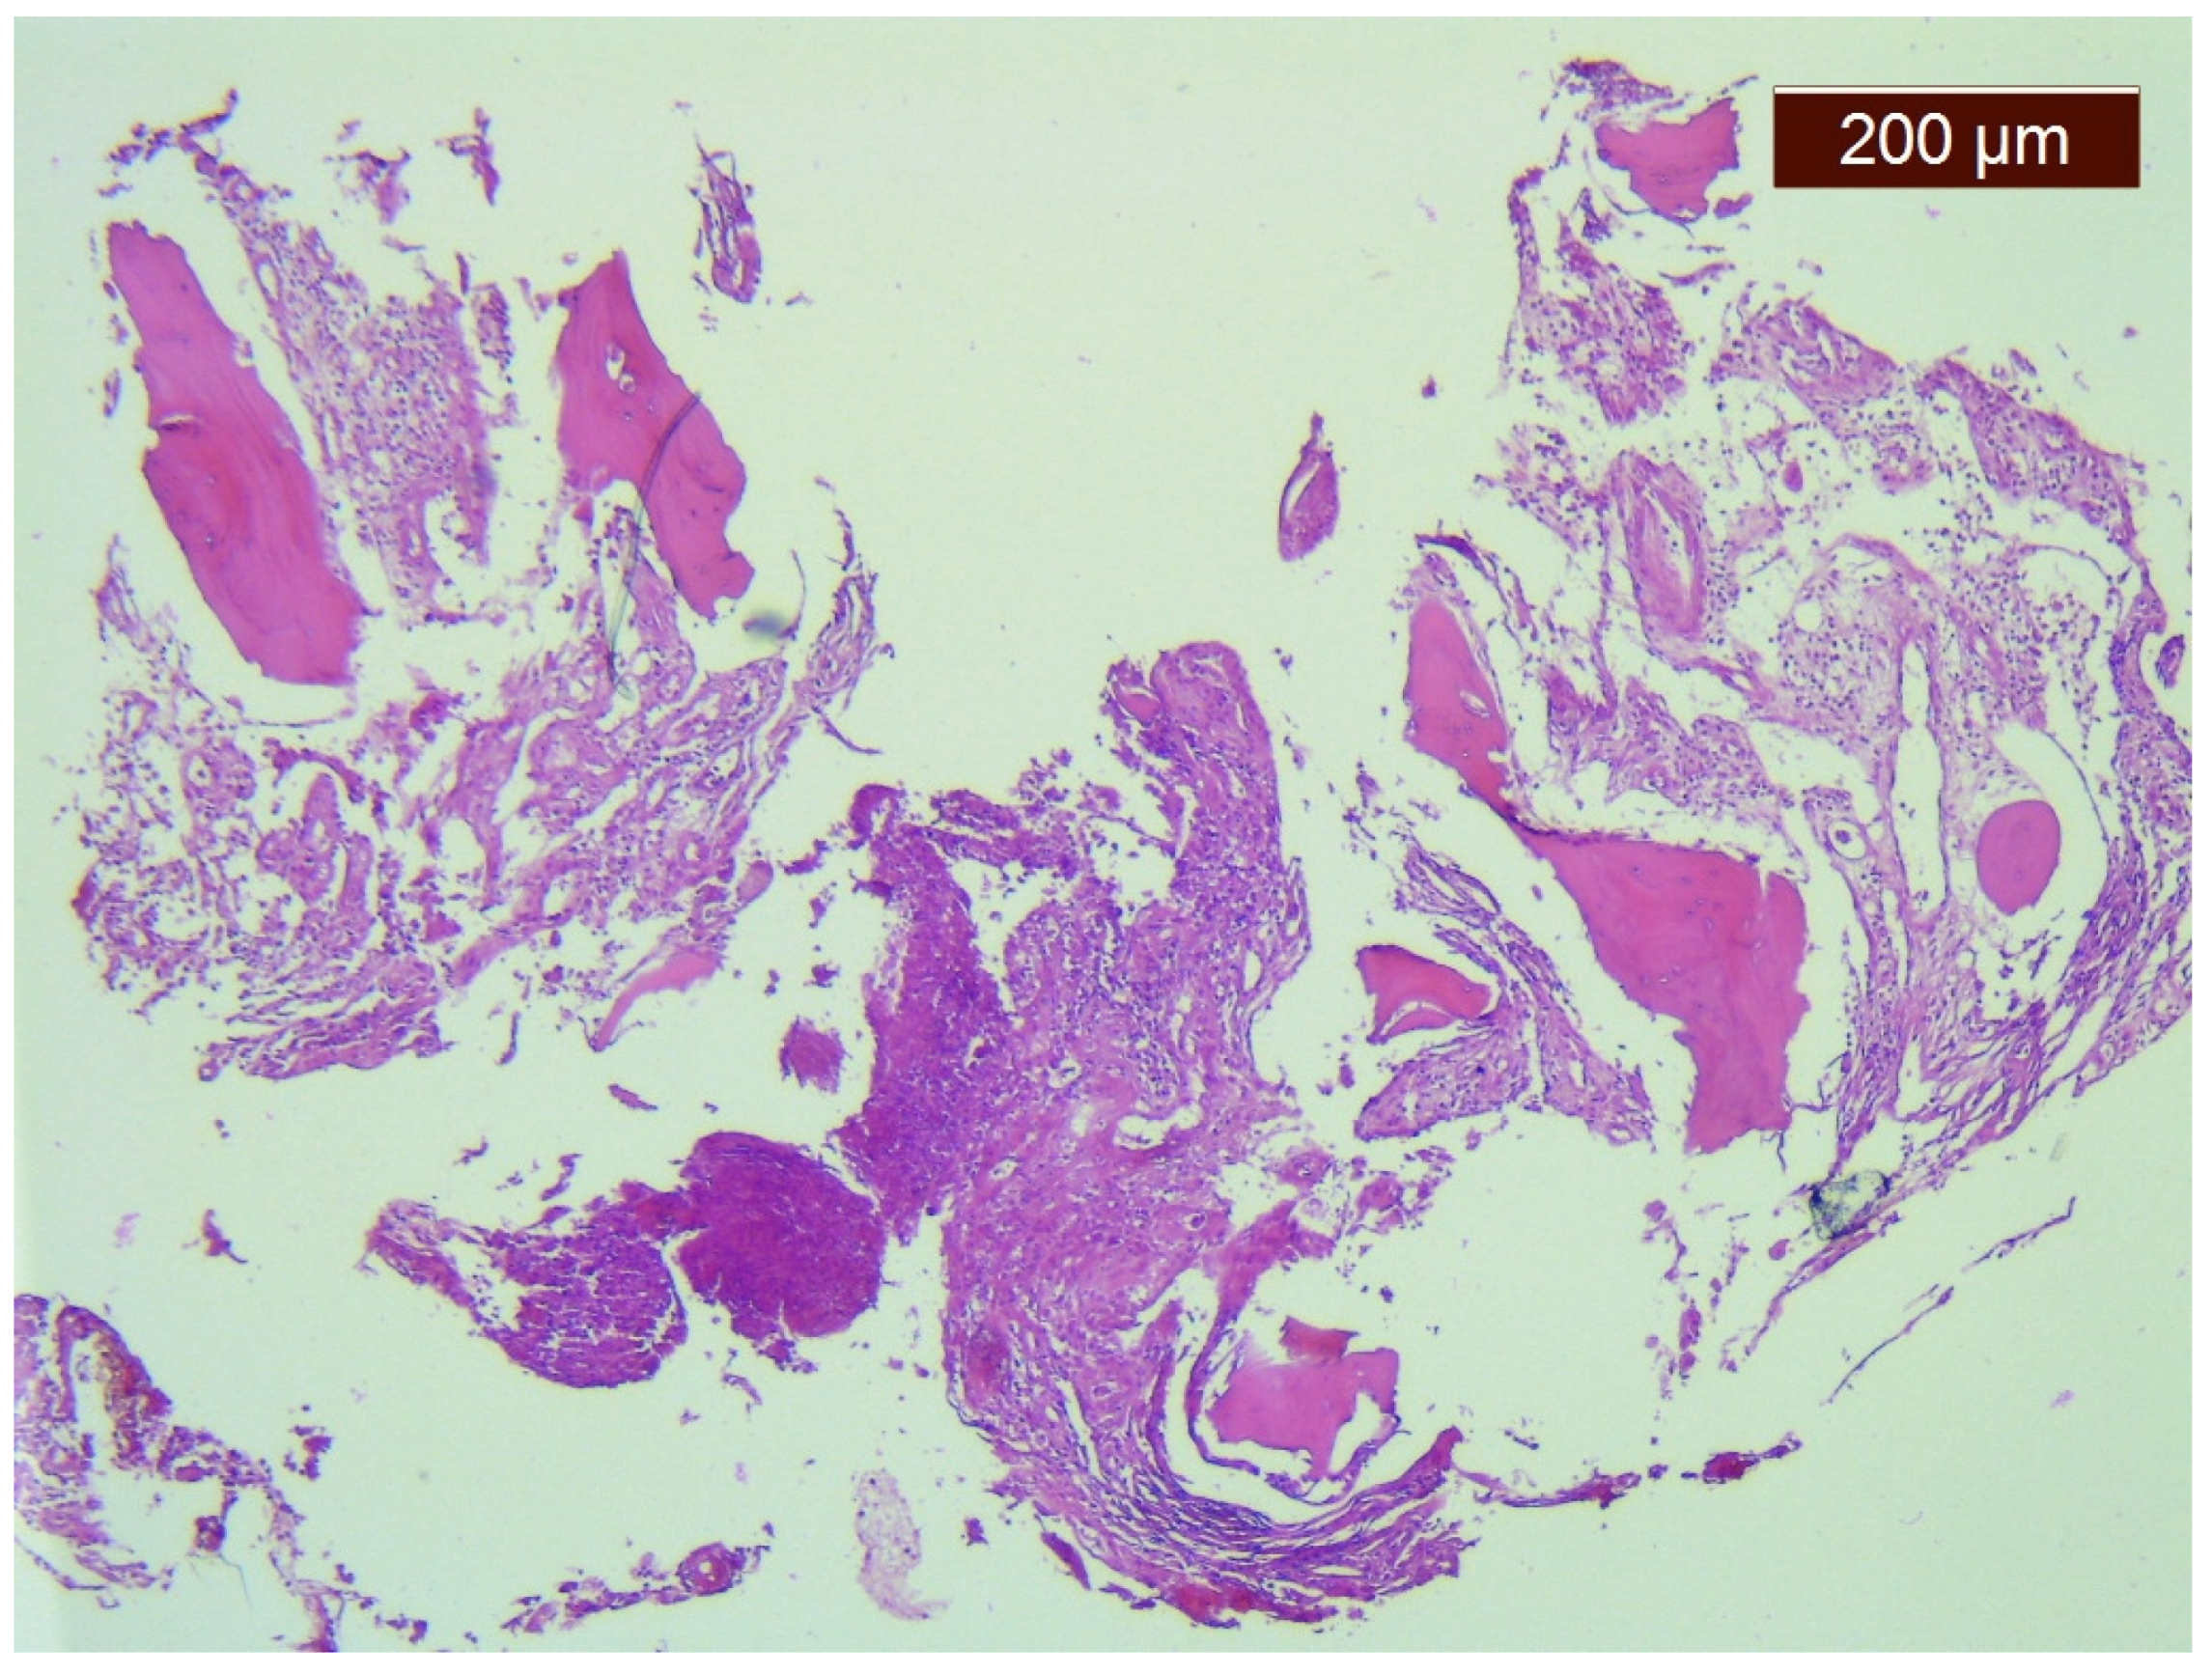

- Moller, G.; Priemel, M.; Amling, M.; Werner, M.; Kuhlmey, A.S.; Delling, G. The Gorham–Stout syndrome (Gorham’smassive osteolysis). A report of six cases with histopathological findings. J. Bone Jt. Surg Br. 1999, 81, 501–506. [Google Scholar] [CrossRef]

- Kawasaki, K.; Ito, T.; Tsuchiya, T.; Takahashi, H. Is angiomatosis an intrinsic pathohistologi- cal feature of massive osteolysis? Report of an autopsy case and a review of the literature. Virchows Arch. 2003, 442, 400–406. [Google Scholar] [CrossRef]